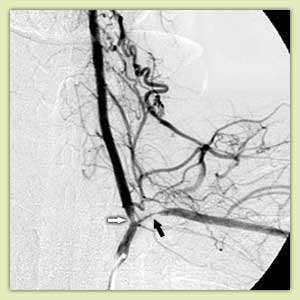

|

Варикоцеле: патологический кровоток по семенной вене (А); окклюзия вены через 30 мин после введения склерозанта (Б) |

Кровоточащая опухоль прямой кишки до (слева) и после (справа) эмболизации. Черными стрелками отмечены введенные в просвет артерии спирали |